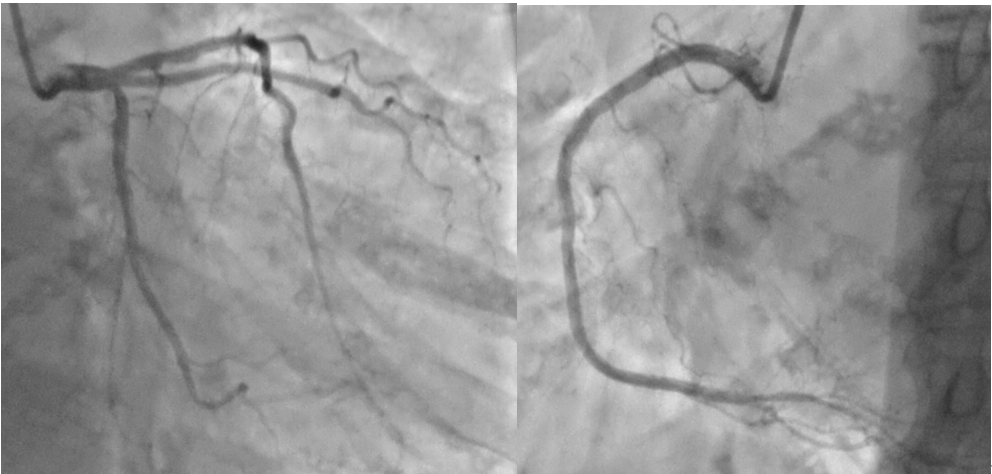

女,73岁,因“阵发性胸闷气短1年,加重1月”入院。既往“高血压”病史10年;冠心病及“糖尿病”病史16年。体格检查:T36.3℃ P55次/分 R16次/分 Bp115/57mmHg H157cm BW65Kg 主动脉瓣听诊区可闻及4/6级喷射样杂音。化验血肌酐107umol/L,余生化结果未见异常。心脏彩超(图1)示重度主动脉瓣狭窄。入院诊断:主动脉瓣重度狭窄、冠心病。冠脉造影(图2)示:前降支近段弥漫性病变伴钙化、最重狭窄50%;回旋支中段弥漫性病变伴钙化、最重狭窄30%;无介入治疗指征。

(图2 术前冠脉造影)